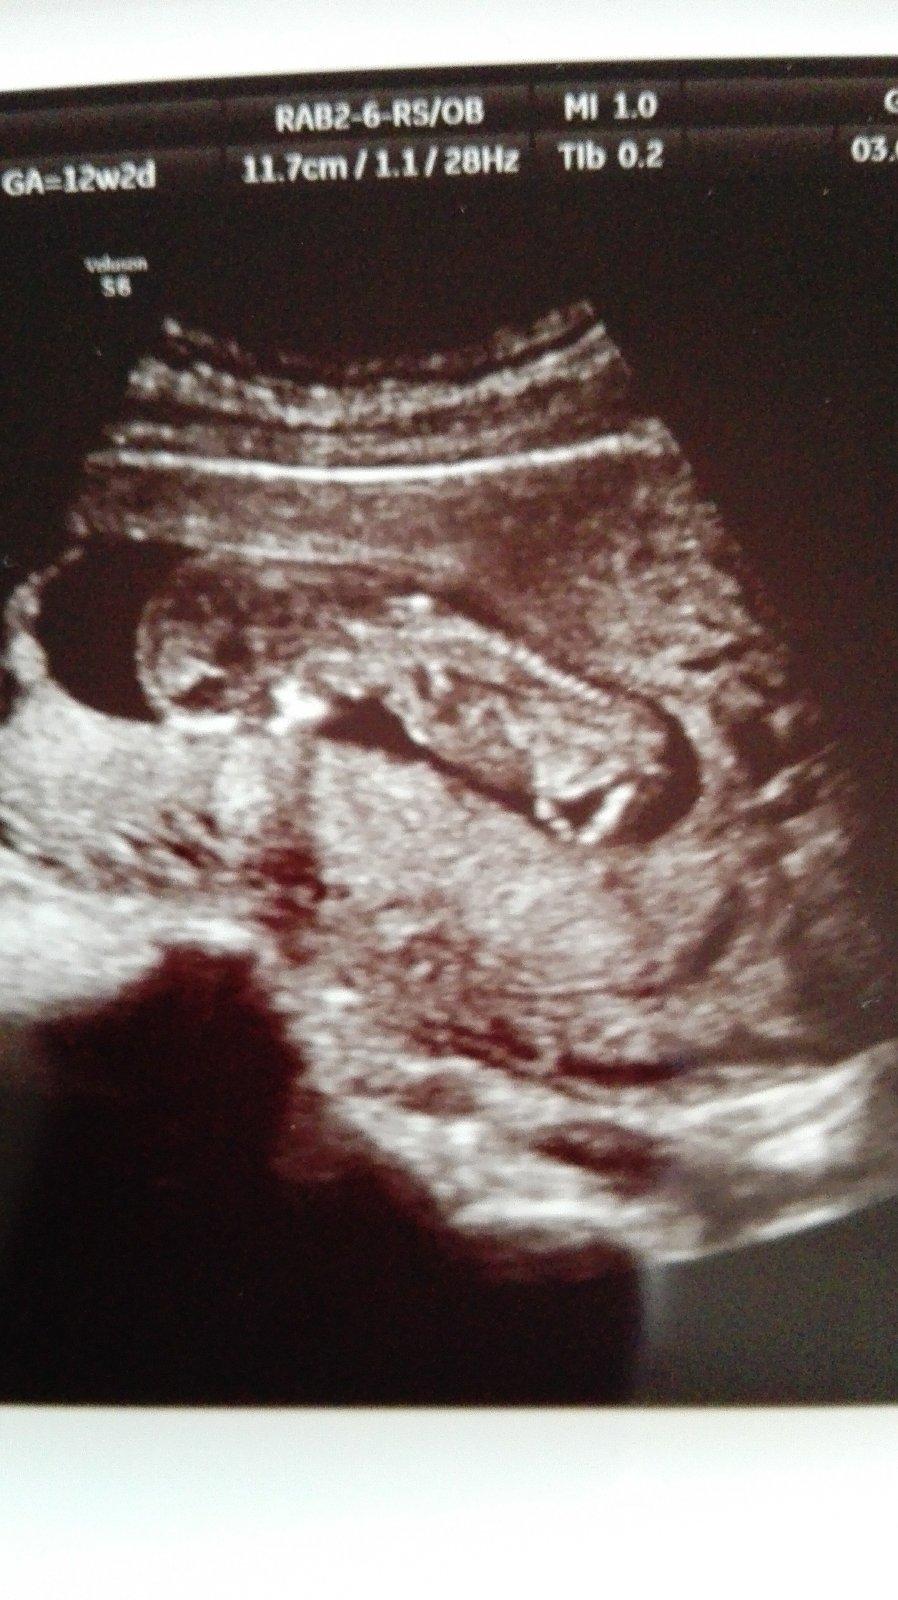

😍 nech sa vam dari 🙂 krasna fotecka 🙂

@zuzuliena1 tešíme sa s tebou 😍

@zuzuliena1 Wwaaaaaw!❤ krásny drobček,naozaj moc sa s Tebou teším 🤗🤗Waw...to už takto bude vyzerať aj moje mimi ?😘😍😇 aký veľký už 😉☺ bože ešte utorok ďaleko...Ale ason že si už môžem doma počúvať srdiečko 🙂 mám to aj krásne nahraté..

@zuzuliena1 jeeeej krasne mimi tak naďalej sa majte pekne v zdraví a šťastí 😉😊